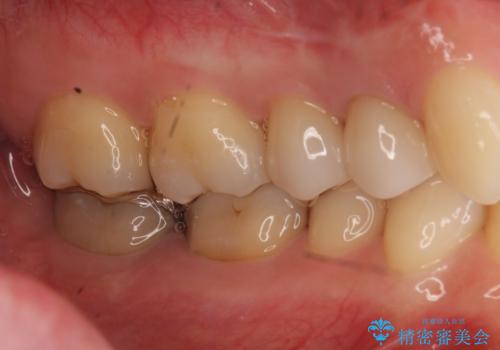

ラバーダム治療ではなかったとのことで、唾液の侵入を防ぐ、当院でのラバーダム治療のメリットを説明しました。

前回の治療がうまくいかなかった原因として、根の中がまだ汚い状態で、根の先だけを切ってもうまくいかない可能性があったことを説明し、根管治療をやり直すことになりました。

必ずしも根管治療がうまく行くかわからないため、抜歯してインプラント(またはブリッジ)にする選択肢もありましたが、なるべく抜歯を避けたいとのことで、根管治療を選択されました。

なお、根管充填にはMTAを使用しました。

術後は瘻孔、圧痛、打診痛も消失し、根尖病変の縮小もみられました。経過良好です。